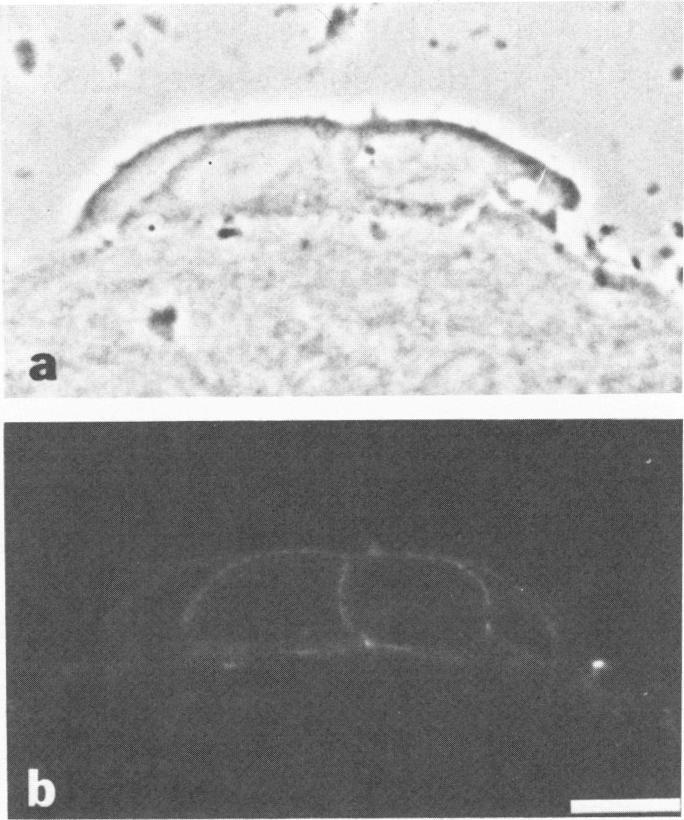

The authors have previously described a transplantable pancreatic acinar carcinoma that comprises cells which reorganize and display normal epithelial orientation only when in contact with basement membrane (BM) in vivo. In the present study, they investigated whether exogenous acellular BM or collagenous stroma (prepared from human amnion) was sufficient to reorient pancreatic acinar tumor cells in vitro. Mechanically dispersed tumor cells could not spontaneously attach to standard culture substrata; yet they adhered to exogenous intact BM or to dishes coated with purified laminin or Type IV collagen. Cell contact with amniotic BM resulted in tumor cell shape changes, assembly of intracellular actin into fibrous bundles, and restoration of normal epithelial cell-cell interactions. Computerized morphometry confirmed that tumor cells exhibited a normal polarized distribution of lipid droplets, nuclei, Golgi complexes, and zymogen granules (from base to apex) within 6 hours of culture on BM. Adhering zonules and microvilli were observed only along apical tumor cell surfaces, although full junctional complexes and distinct membrane domains did not reform. Similar attachment, cytoskeletal alterations, and reorientation occurred in the absence of protein synthesis (25 micrograms/ml cycloheximide). In contrast, tumor cells that were maintained on amniotic stroma remained round, displayed circumferential rings of actin, and appeared randomly oriented. Thus, BM may normally serve to integrate and maintain individual cells within a polarized epithelium.